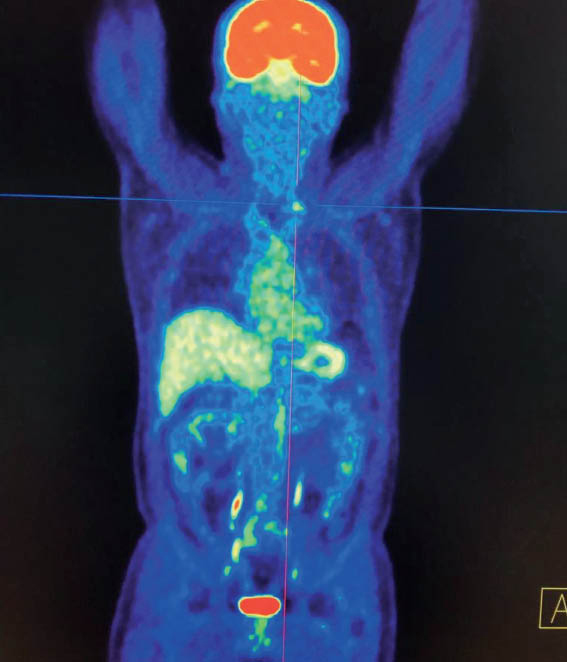

В якості ілюстрації наводимо клінічні випадки проведення ПЕТ / КТ з 18F-ФДГ у пацієнтів з йод-негативними вогнищами ДРЩЗ, виявленими іншими методами дослідження.

Хворий А., папілярний рак щитоподібної залози, 4 курси РЙТ, відсутність накопичення 131I-NaI на постлікувальному скані після 3-го курсу. За даними УЗД та КТ обстеження — підозра на можливі вогнища в зоні шиї та легень. Хворому призначено ПЕТ / КТ з 18F-ФДГ (рис. 2).

Рис. 2. ПЕТ / КТ з 18F-ФДГ. Візуалізується вогнище в зоні шиї

За даними ПЕТ / КТ з 18F-ФДГ у цього пацієнта підтверджена наявність вогнища гіперфіксації РФП в зоні шиї, водночас не виявлено ознак пролонгації процесу в легенях. Вірогідно, знайдені вогнища, за даними КТ, відповідають фіброзним змінам після перенесених запальних процесів.